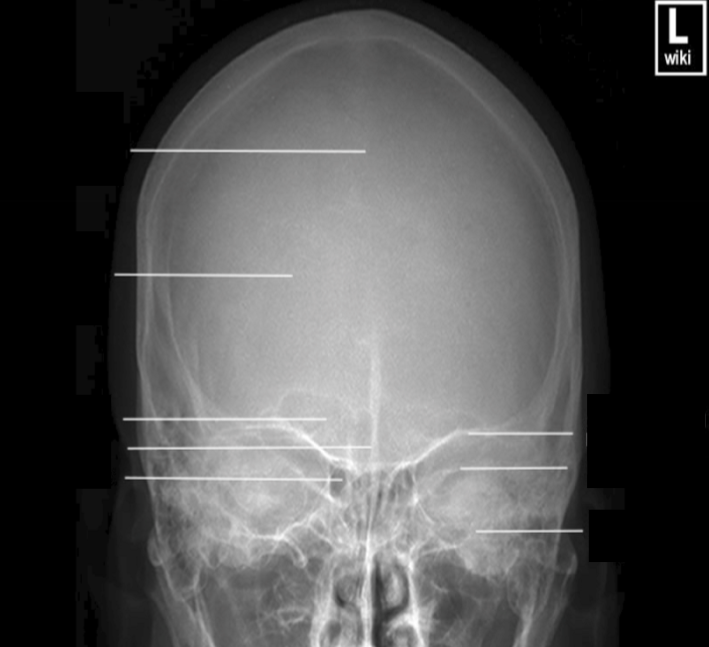

Please label